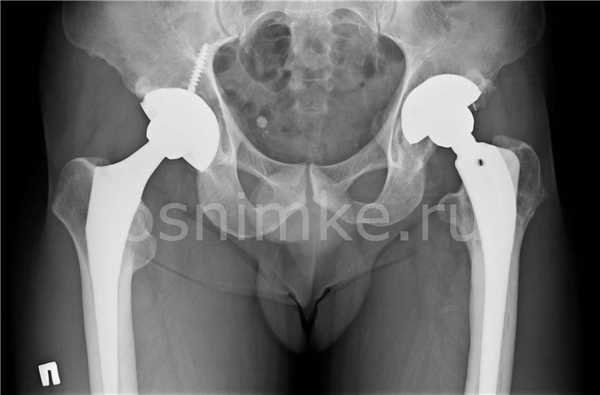

Эндопротезирование тазобедренного сустава